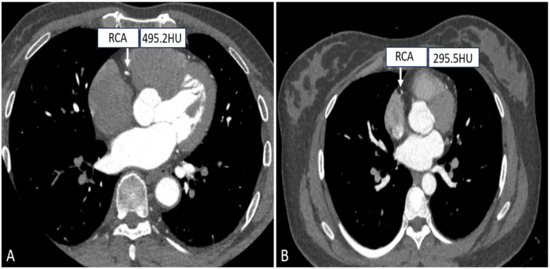

- Wang, X.; Yang, F.; Zhu, Y.; Xiao, Z.; Cui, S. Feasibility Research of Low Concentration Contrast Agent Iodixanol (270 mg I/mL) Combined with the Lower Tube Voltage in Coronary CTA with 640-slice Volumetric CT. J. Hebei North Univ. (Nat. Sci. Ed.) 2018, 83, e92–e99. [Google Scholar]